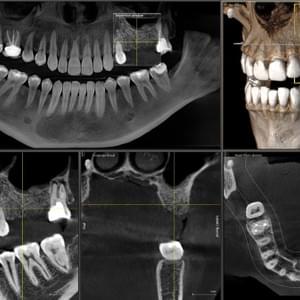

Scanner Cone-Beam CT de última generación

Panorámicas, teleradiografias y CBCT con el sensor más moderno, preciso y de baja dosis.